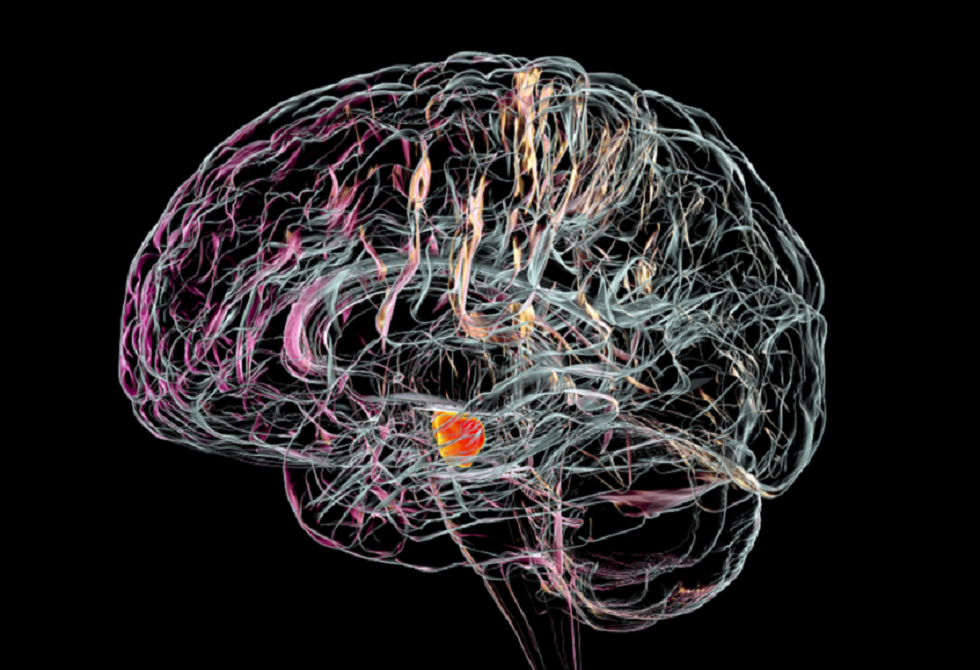

علاقة مقلقة بين نوع مياه الشرب وزيادة خطر مرض عصبي مزمن

أظهرت دراسة حديثة أن نوع مياه الشرب التي يتناولها الإنسان قد يكون له علاقة بزيادة خطر الإصابة بمرض باركنسون.

ويعرف مرض باركنسون بأنه اضطراب عصبي مزمن يسبب الرعاش وصعوبة في الحركة والتوازن وتيبس العضلات ومشاكل في الكلام، وتتفاقم أعراضه مع مرور الوقت.

وفي الدراسة، ركز باحثون من مدينة نيويورك وأريزونا على تحليل تأثير مصادر المياه الجوفية على هذا المرض.

ودرس الفريق أكثر من 12 ألف شخص مصاب بباركنسون، وأكثر من مليون شخص غير مصابين، جميعهم يعيشون بالقرب من مواقع أخذ عينات المياه الجوفية لمراقبة جودتها.

وأظهرت النتائج أن الأشخاص الذين يحصلون على مياههم من مواقع المياه الجوفية الحديثة — أي التي أُنشئت خلال الـ 75 عاما الماضية — كانوا أكثر عرضة بنسبة 11% للإصابة بالمرض مقارنة بمن يحصلون على المياه من المصادر القديمة. كما تبين أن شرب المياه من طبقات المياه الجوفية الكربوناتية، وهي طبقات صخرية قابلة للذوبان تحمل المياه، يزيد من خطر الإصابة بنسبة تصل إلى 62% مقارنة بالمياه من الطبقات الجليدية.

ويعتقد الخبراء أن المياه الجوفية القديمة أكثر نقاء لأنها تأتي من أعماق أكبر، ما يحميها من الملوثات مثل المعادن الثقيلة والمبيدات الحشرية.

وتنتشر طبقات المياه الجوفية بشكل واسع في الولايات المتحدة، حيث تخدم نحو 145 مليون شخص، ويأتي حوالي نصف مياه الشرب في البلاد من هذه المصادر. ويُعتقد أن طبقات المياه الجوفية الجليدية، التي تشكلت أثناء العصر الجليدي، تعمل كمرشح طبيعي بفضل تكوينها من الرمل والحصى، ما يقلل من تلوث المياه.

وأكدت بريتاني كرزيزانوفسكي، معدة الدراسة والباحثة في معهد أتريا للأبحاث في نيويورك، أن "إحدى طرق دراسة التعرض للتلوث الحديث هي من خلال مياه الشرب. المياه الجوفية الحديثة، الناتجة عن أمطار السبعين إلى الخمسة والسبعين عاما الماضية، تتعرض لمزيد من الملوثات، بينما المياه القديمة تبقى أنظف إذا كانت محمية بعمق. وجدت دراستنا أن عمر المياه الجوفية وموقعها يعدّان من عوامل الخطر البيئية المحتملة لمرض باركنسون".

ولفتت الدراسة إلى أن نحو 3463 من المصابين بمرض باركنسون يحصلون على مياه الشرب من طبقات المياه الجوفية الكربوناتية، و515 من طبقات المياه الجوفية الجليدية، و8329 من طبقات مياه جوفية أخرى. بينما بين غير المصابين، حصل 300264 على المياه الكربوناتية، و62917 على المياه الجليدية، و860993 على مصادر أخرى.

وحذر الباحثون من أن الدراسة لا تثبت أن المياه الحديثة تسبب باركنسون، لكنها تشير إلى وجود ارتباط محتمل بين نوع الماء وخطر الإصابة، خاصة عند التعرض الطويل للمياه الجوفية الحديثة والملوثة. ويُنصح بغلي المياه أو استخدام فلاتر منزلية للحد من الملوثات.